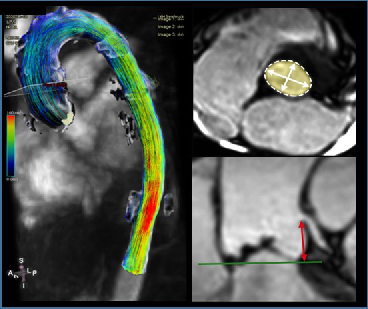

Cardiovascular MR Imaging

Agnes Mayr, Christian Kremser, in cooperation with the Department of Cardiology

a) STEMI CMR: CMR Parameters of Myocardial Tissue Damage in ST-Elevation Myocardial Infarction (STEMI).

Since 2005, almost 900 patients have been examined under a comprehensive cardiac MRI (CMR) protocol within the first week as well as 4 months, 12 months and 10 years after acute STEMI. In more than 60 internal original papers, CMR myocardial infarction severity markers were assessed and the effects of CMR on optimised risk assessment shortly after STEMI were evaluated.

b) TAVI CMR: CMR to Guide Transcatheter Aortic Valve Implantation (TAVI).

This ongoing randomised study investigates the non-inferiority of TAVI CMR to TAVI CT for the first time, with regard to efficacy and safety end-points in the guidance for TAVI evaluation.

c) 4D Phase Contrast Flow Measurements

• Patients with different grades of aortic valve stenosis: comparison of 4D flow-assessed stenosis severity with 3D echocardiography and invasive measurements.

• Patients with cryptogenic stroke: recording turbulent kinetic energy, changes in flow patterns and regional wall stresses as well as occurrence of a vortex-shaped flow along the thoracic aortic wall, in order to optimise the elucidation of potential cardioembolic sources.